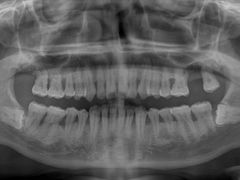

• 牙博士口腔品牌连锁(杨浦店)

• -牙博士口腔品牌连锁(杨浦店)

pudding蕊_4175 | 20-12-27

报错